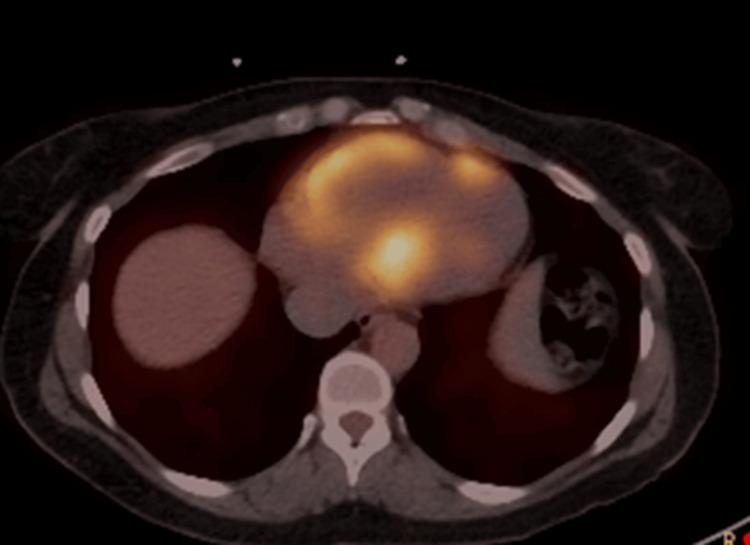

The clinical and imaging features of cardiac sarcoidosis (CS) and giant cell myocarditis (GCM) are occasionally indistinguishable. This is a case of heart block and ventricular tachycardia where cardiac MRI, fluorodeoxyglucose positron emission tomography (FDG-PET) and biopsy revealed intermediate clinicohistologic phenotype between CS and GCM. This highlights gaps in the management of overlap conditions.

心脏结节病(CS)和巨细胞性心肌炎(GCM)的临床及影像学特征有时难以区分。本文报告一例心脏传导阻滞和室性心动过速患者,心脏磁共振成像(MRI)、氟脱氧葡萄糖正电子发射断层扫描(FDG-PET)及活检显示其临床组织学表型介于CS和GCM之间。这凸显了重叠病症管理方面的差距。